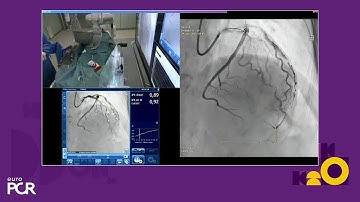

ACC 23: RENOVATE-COMPLEX-PCI: IVUS Vs OCT Optimisation in Complex PCI